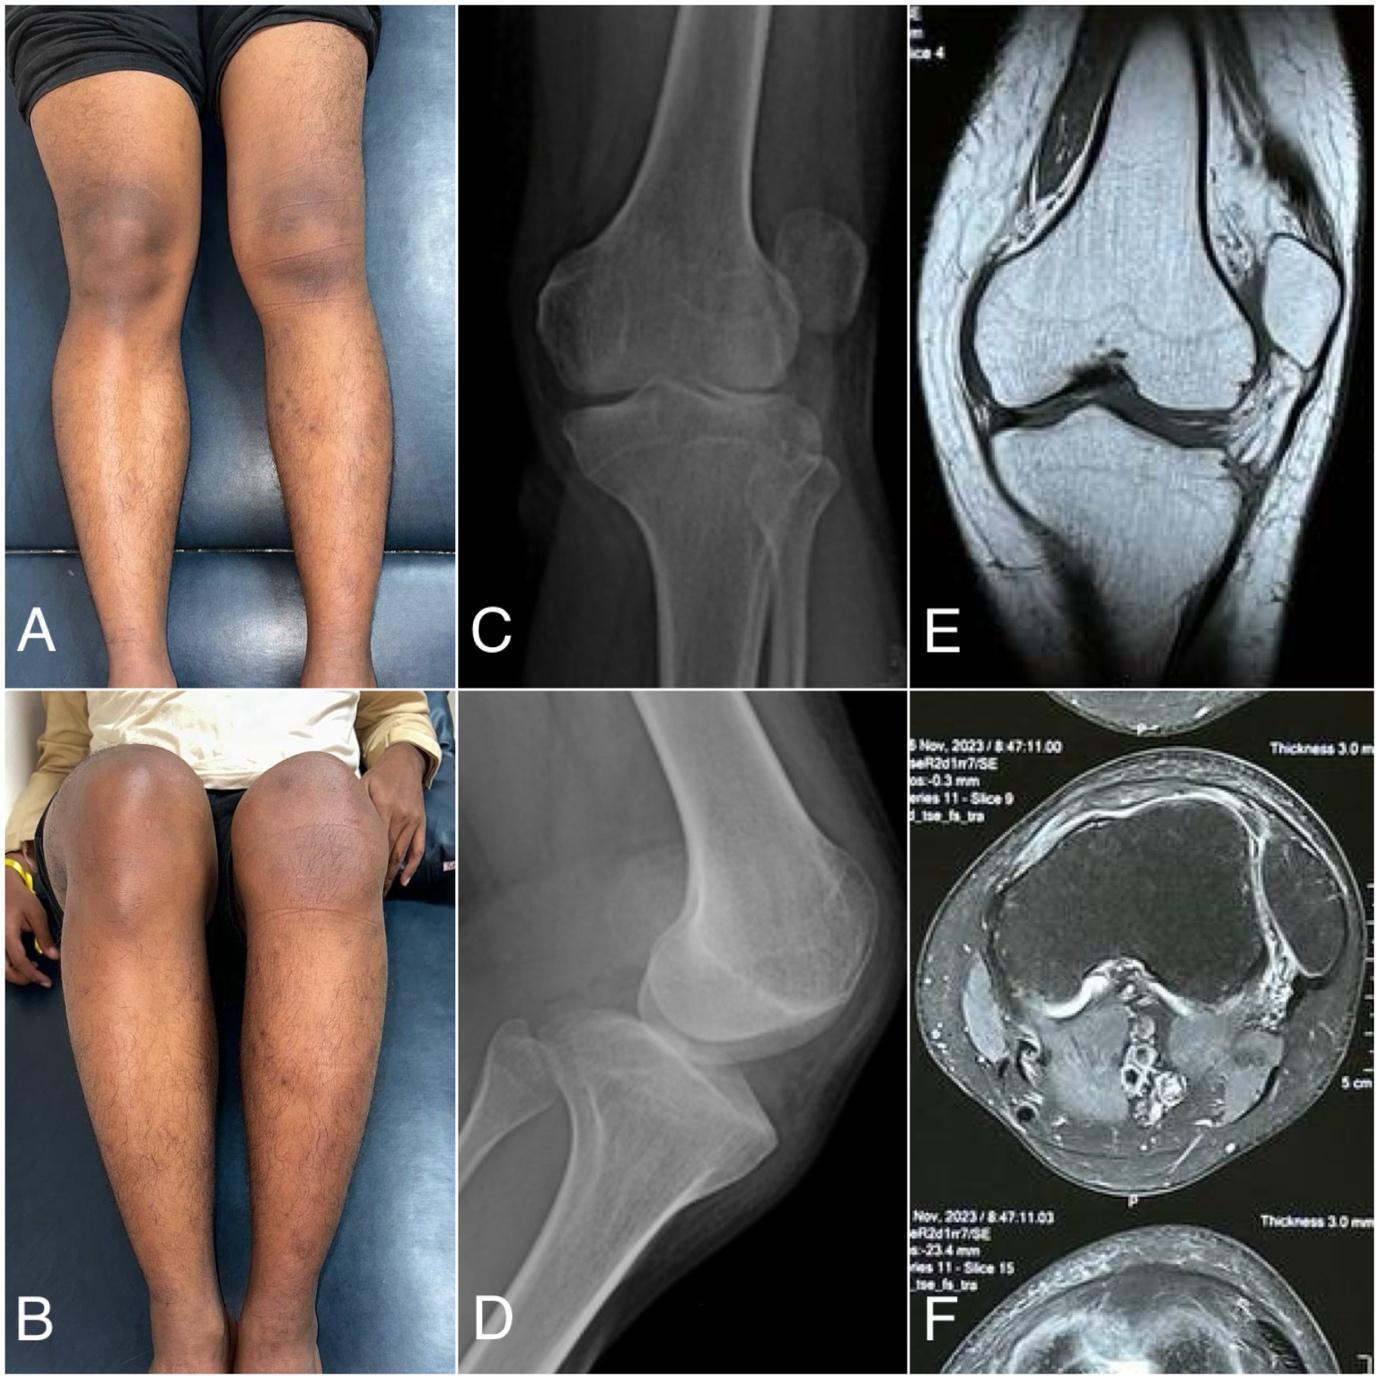

The physical examination showed a deformity of the left knee, and a J-track sign was visualized on his lateral side of the left knee (Fig 1A, 1B). The apprehension test showed a positive sign of lateral dislocation of the patella but without pain. The passive lateral patellar tilt test yielded a negative result due to the widespread stiffness and tightness of the soft tissue connection along the lateral border of the patella. There was no swelling, but the patella was clearly palpable on the lateral knee. Only 75 degrees of knee flexion range of motion and 20 degrees of knee extension range of motion from the horizontal axis. Clinical scoring using the Tegner Lysholm score of 69 and the IKDC score of 62.1, which indicating moderate functional limitation. Anteroposterior and lateral knee radiographs, as well as coronal and axial MRI scans, revealed a patellar lateral dislocation associated with trochlear dysplasia (Fig 1).